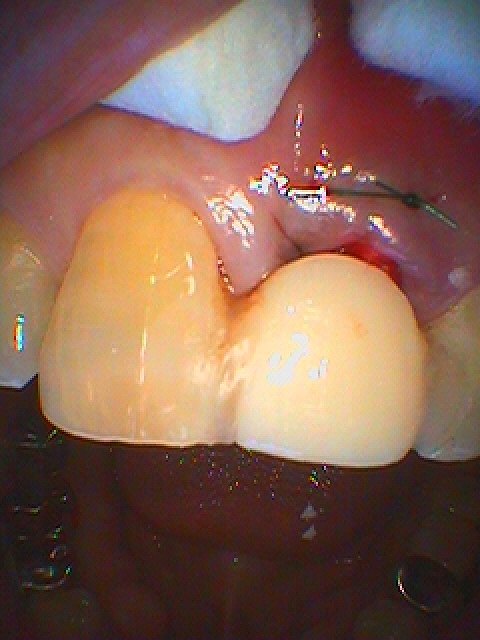

仮歯をレスカンツァにて作成し両臨在歯に留めています

舌側から